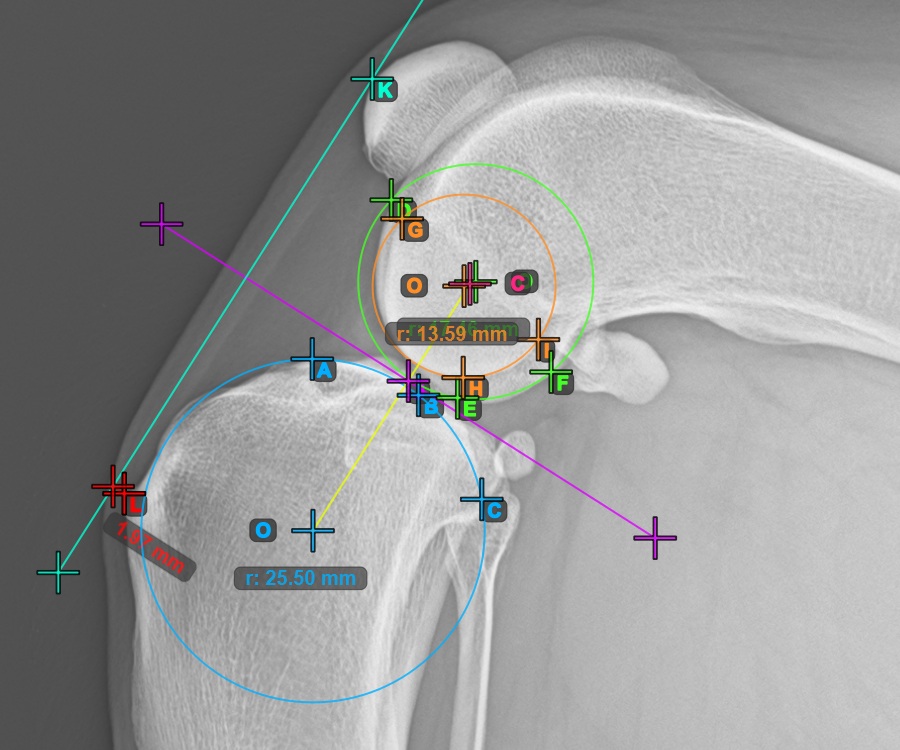

Markieren Sie einen Punkt vor dem Gelenk auf der gemeinsamen Tangente zwischen den beiden Hauptkondyluskreisen. Eine Linie wird automatisch durch den markierten Punkt gezogen.

Das Bild unten zeigt die typische Platzierung des Punkts auf der gemeinsamen Tangente zwischen den beiden Kreisen.